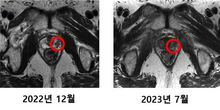

연세암병원, 국내 첫 중입자치료 환자의 암 조직 제거 확인